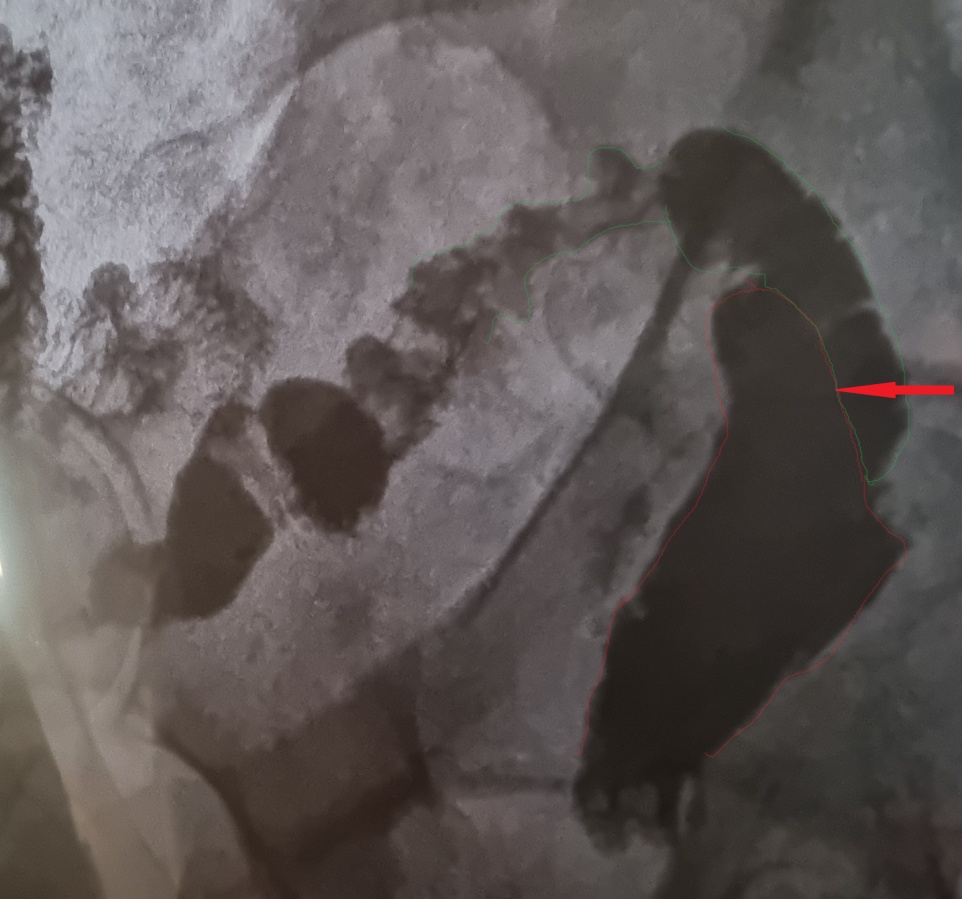

Μετεγχειρητική απεικόνιση ειλεορθικής αναστόμωσης (τροποποιημένη Duhamel). Εμφανής η αναστόμωση του τερματικού ειλεού στο πρόσθιο τοίχωμα του εναπομένοντος κολοβώματος ορθού (Ευγενική παραχώρηση Dr. V. Penopoulos)